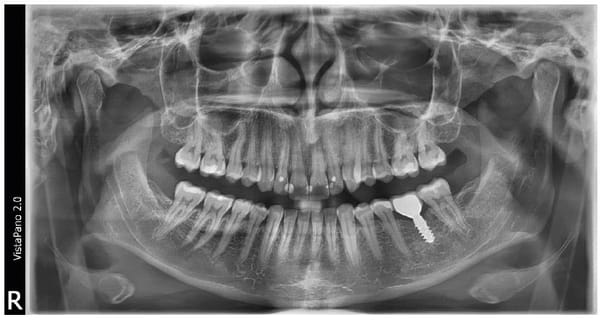

La technologie S-Pan : des images d'une netteté exceptionnelle pour des diagnostics sûrs

Contrairement à la méthode traditionnelle, la technologie S-Pan sélectionne automatiquement, parmi de nombreuses couches parallèles, les sections d’image qui représentent le mieux l’anatomie individuelle du patient. Lors de l’assemblage de l’image panoramique, les écarts par rapport à la « dentition moyenne » sont également pris en compte, tout comme l’inclinaison individuelle des dents. On obtient, par conséquent, une image d’une clarté exceptionnelle qui permet au dentiste de trouver immédiatement les structures pertinentes. Comme la reconstruction s'oriente en fonction de la situation effective de la dentition, les erreurs de positionnement sont « compensées » dans certaines limites. Ainsi, le cabinet gagne du temps, et le client ne subit aucune répétition de clichés.

Comparaison de la technologie S-Pan